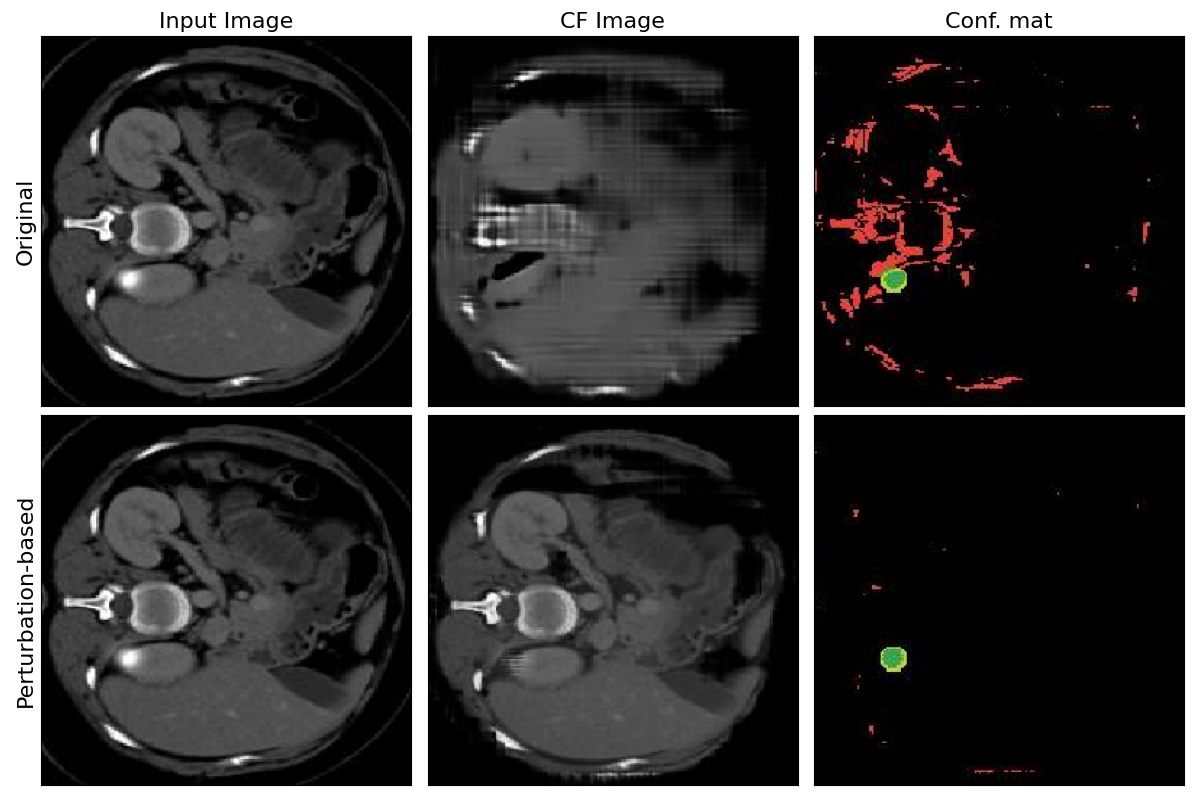

Refer to caption

Figure 4: Examples of images generated with original and perturbation-based Singla et al.* pipelines.

Within this experiment, the counterfactual explainer of Singla et al. is taken to validate the significant improvement employing the perturbation-based generation in terms of FID and IoU scores. The perturbation-based image generation generates much higher fidelity images. Instead of reconstructing the whole input image from scratch, the decoder learns to output only the changes needed to flip classifier decision. Figure 4 gives qualitative evaluation of the generated images following the two approaches.

Figure 5: Examples of images generated with and without skip-connections between encoder-decoder layers of the perturbation-based Singla et al.* pipeline.

In this experiment, the baseline of Singla et al. employing perturbation-based counterfactual generation from the previous section is taken to showcase the importance of skip connections in the generator network to mitigate drastic distortions of the input images. During the down-sampling process of the encoder, the information loss is inevitable, so reconstructing the counterfactual images with minimum perturbations becomes a challenge. Therefore, the skip connections between different down-sampling and up-sampling layers are gradually injected to show the improvements in terms of FID and IoU scores. The perturbation-based image generation leveraging skip connections results in less distorted images, hence, in lower FID score. Figure 5 gives qualitative evaluation of the generated images with and without adoption of skip-connections.